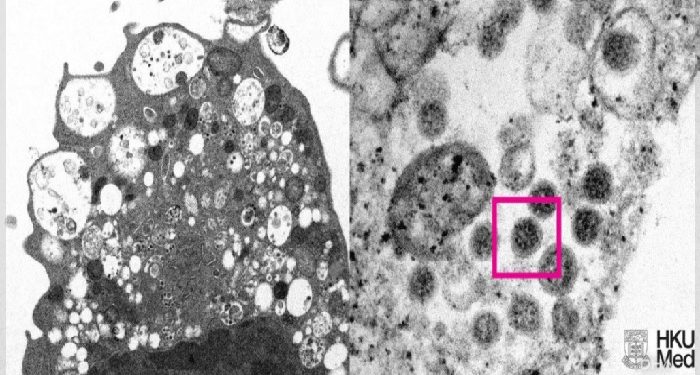

Hong Kong Üniversitesi Li Ka Shing Tıp Fakültesi (HKUMed) tarafından Omicron varyantının elektron mikroskobu görüntüsünün ortaya çıkarıldığı duyuruldu.

HKUMed’den yapılan açıklamada, araştırmacılar tarafından SARS-CoV-2 virüsünün Omicron varyantının elektron mikroskobu görüntüsünün ortaya çıkarıldığı belirtildi.

Üniversite tarafından yayınlanan fotoğrafın solunda, küçük siyah viral partiküller içeren şişmiş veziküllerle hücre hasarını gösteren, SARS-CoV-2 Omicron varyantı ile enfeksiyondan sonra bir maymun böbrek hücresinin (Vero E6) düşük büyütmeli elektron mikrografının yer aldığı ifade edildi. Fotoğrafın sağında ise yüzeylerinde korona şekilli sivri uçlara sahip viral partikül kümelerini gösteren enfekte bir Vero E6 hücresinin yüksek büyütmeli elektron mikrografının yer aldığı belirtildi.